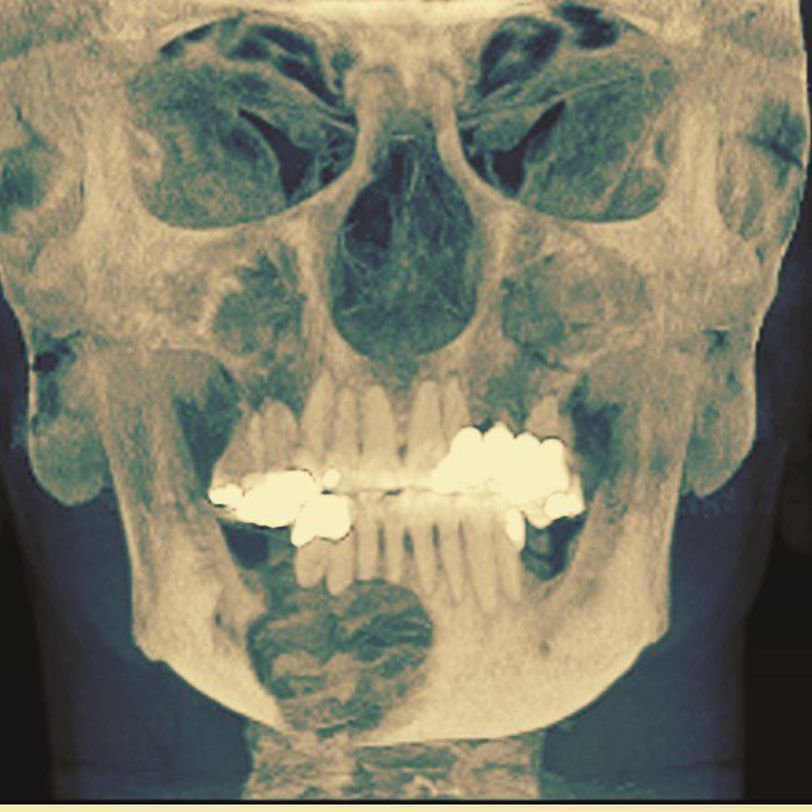

Easily one of the most beautiful and unique structures in the natural world ππ Depicted here is an expansile radiolucent lesion of the mandible. These jaw lesions are commonly referred to oral & maxillofacial surgeons for not only treatment of the pathology, but the reconstructive surgery as well π Oral and Maxillofacial Surgeonsβ experience in both dental and medical education allows comprehensive treatment of underlying disease while preserving and respecting the dental occlusion, form, and function βοΈπ